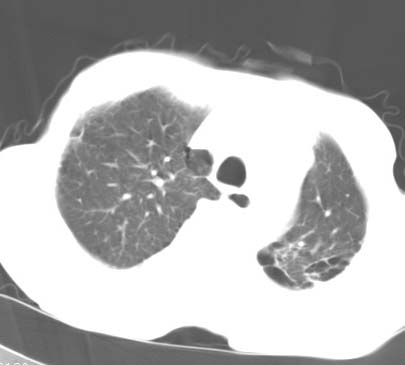

标题: CT14816:男性81岁 胸痛 咳嗽2月 2周前提示右下肺感染. [打印本页]

标题: CT14816:男性81岁 胸痛 咳嗽2月 2周前提示右下肺感染.

男性病人 81岁 胸痛 咳嗽2月 2周前提示右下肺感染.

今片ct示双肺多发结节影 可以这样诊断吗?1\双肺感染性病变 结核待排.

2\双肺纤维硬结灶,左肺肺气肿.

3\肺间质纤维化,胸膜肥厚粘连.

纵隔左移双肺上叶纤维硬结,肺气肿,双侧斑痕肺大泡,双侧胸膜增厚并胸膜下陈旧性病灶,右肺下叶胸膜下小结节影,密度较淡,建议复查.

病人桶状胸,胸廓肌肉消瘦;两上肺均可见纤维条索灶,下肺外围胸膜下可见间质纤维化改变,右下肺沿肺纹理分部结节样病灶,边缘光滑,考虑1、慢支并局灶性间质纤维化、右下肺合并感染,2、两上肺为陈旧性肺结核灶并瘢痕旁型肺气肿3、右下肺转移瘤待排。

两肺上叶见多发索条状高密度影,右肺下叶见片状、结节状高密度影,两肺体积增大,胸膜下区见囊状低密度影、内有分隔结构。左肺下叶见网格影。两侧胸膜见增厚影。诊断:两肺继发性肺结核。慢性支气管炎合并感染。肺气肿。肺间质纤维化。胸膜增厚。